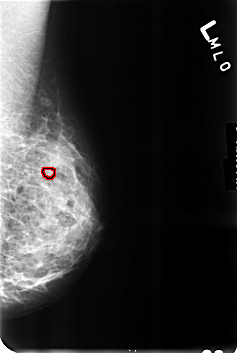

B_3231_1.LEFT_MLO

FILE: B_3231_1.LEFT_MLO.OVERLAY

TOTAL_ABNORMALITIES 1

ABNORMALITY 1

LESION_TYPE CALCIFICATION TYPE PUNCTATE DISTRIBUTION N/A

ASSESSMENT 2

SUBTLETY 4

PATHOLOGY BENIGN_WITHOUT_CALLBACK

TOTAL_OUTLINES 1

BOUNDARY